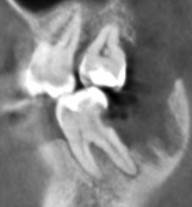

Александр9 Опубликовано 24 ноября, 2021 Автор Поделиться Опубликовано 24 ноября, 2021 спасибо за ответы! Впервые наблюдал за лечением своего зуба на экране. С микроскопом оказалось действительно лучше, т.к. зуб достаточно глубоко был поражен и приходилось тщательно его "вычищать" изнутри. Правда в стенке все же образовалась дырка и пришлось ее заделывать "заплаткой". На снимке видно темные области под временной пломбой. Это не помешает проходить с ней 4 месяца до установки коронки? 1 Ссылка на комментарий

St. Опубликовано 26 ноября, 2021 Поделиться Опубликовано 26 ноября, 2021 По снимку все красиво! Под такой временной пломбой может быть неконтрастный материал или "ваточка". Тем не менее долго ходить с временной пломбой не стоит и чем быстрее Вы попадете на восстановление и коронку тем лучше (меньше риск что отколите остатки стенок и повторного попадения микробов). Кстати, если вдруг временная выпадет, обязательно показаться доктору и вернуть ее на место. без временной ходить категорически нельзя. 1 1 Ссылка на комментарий